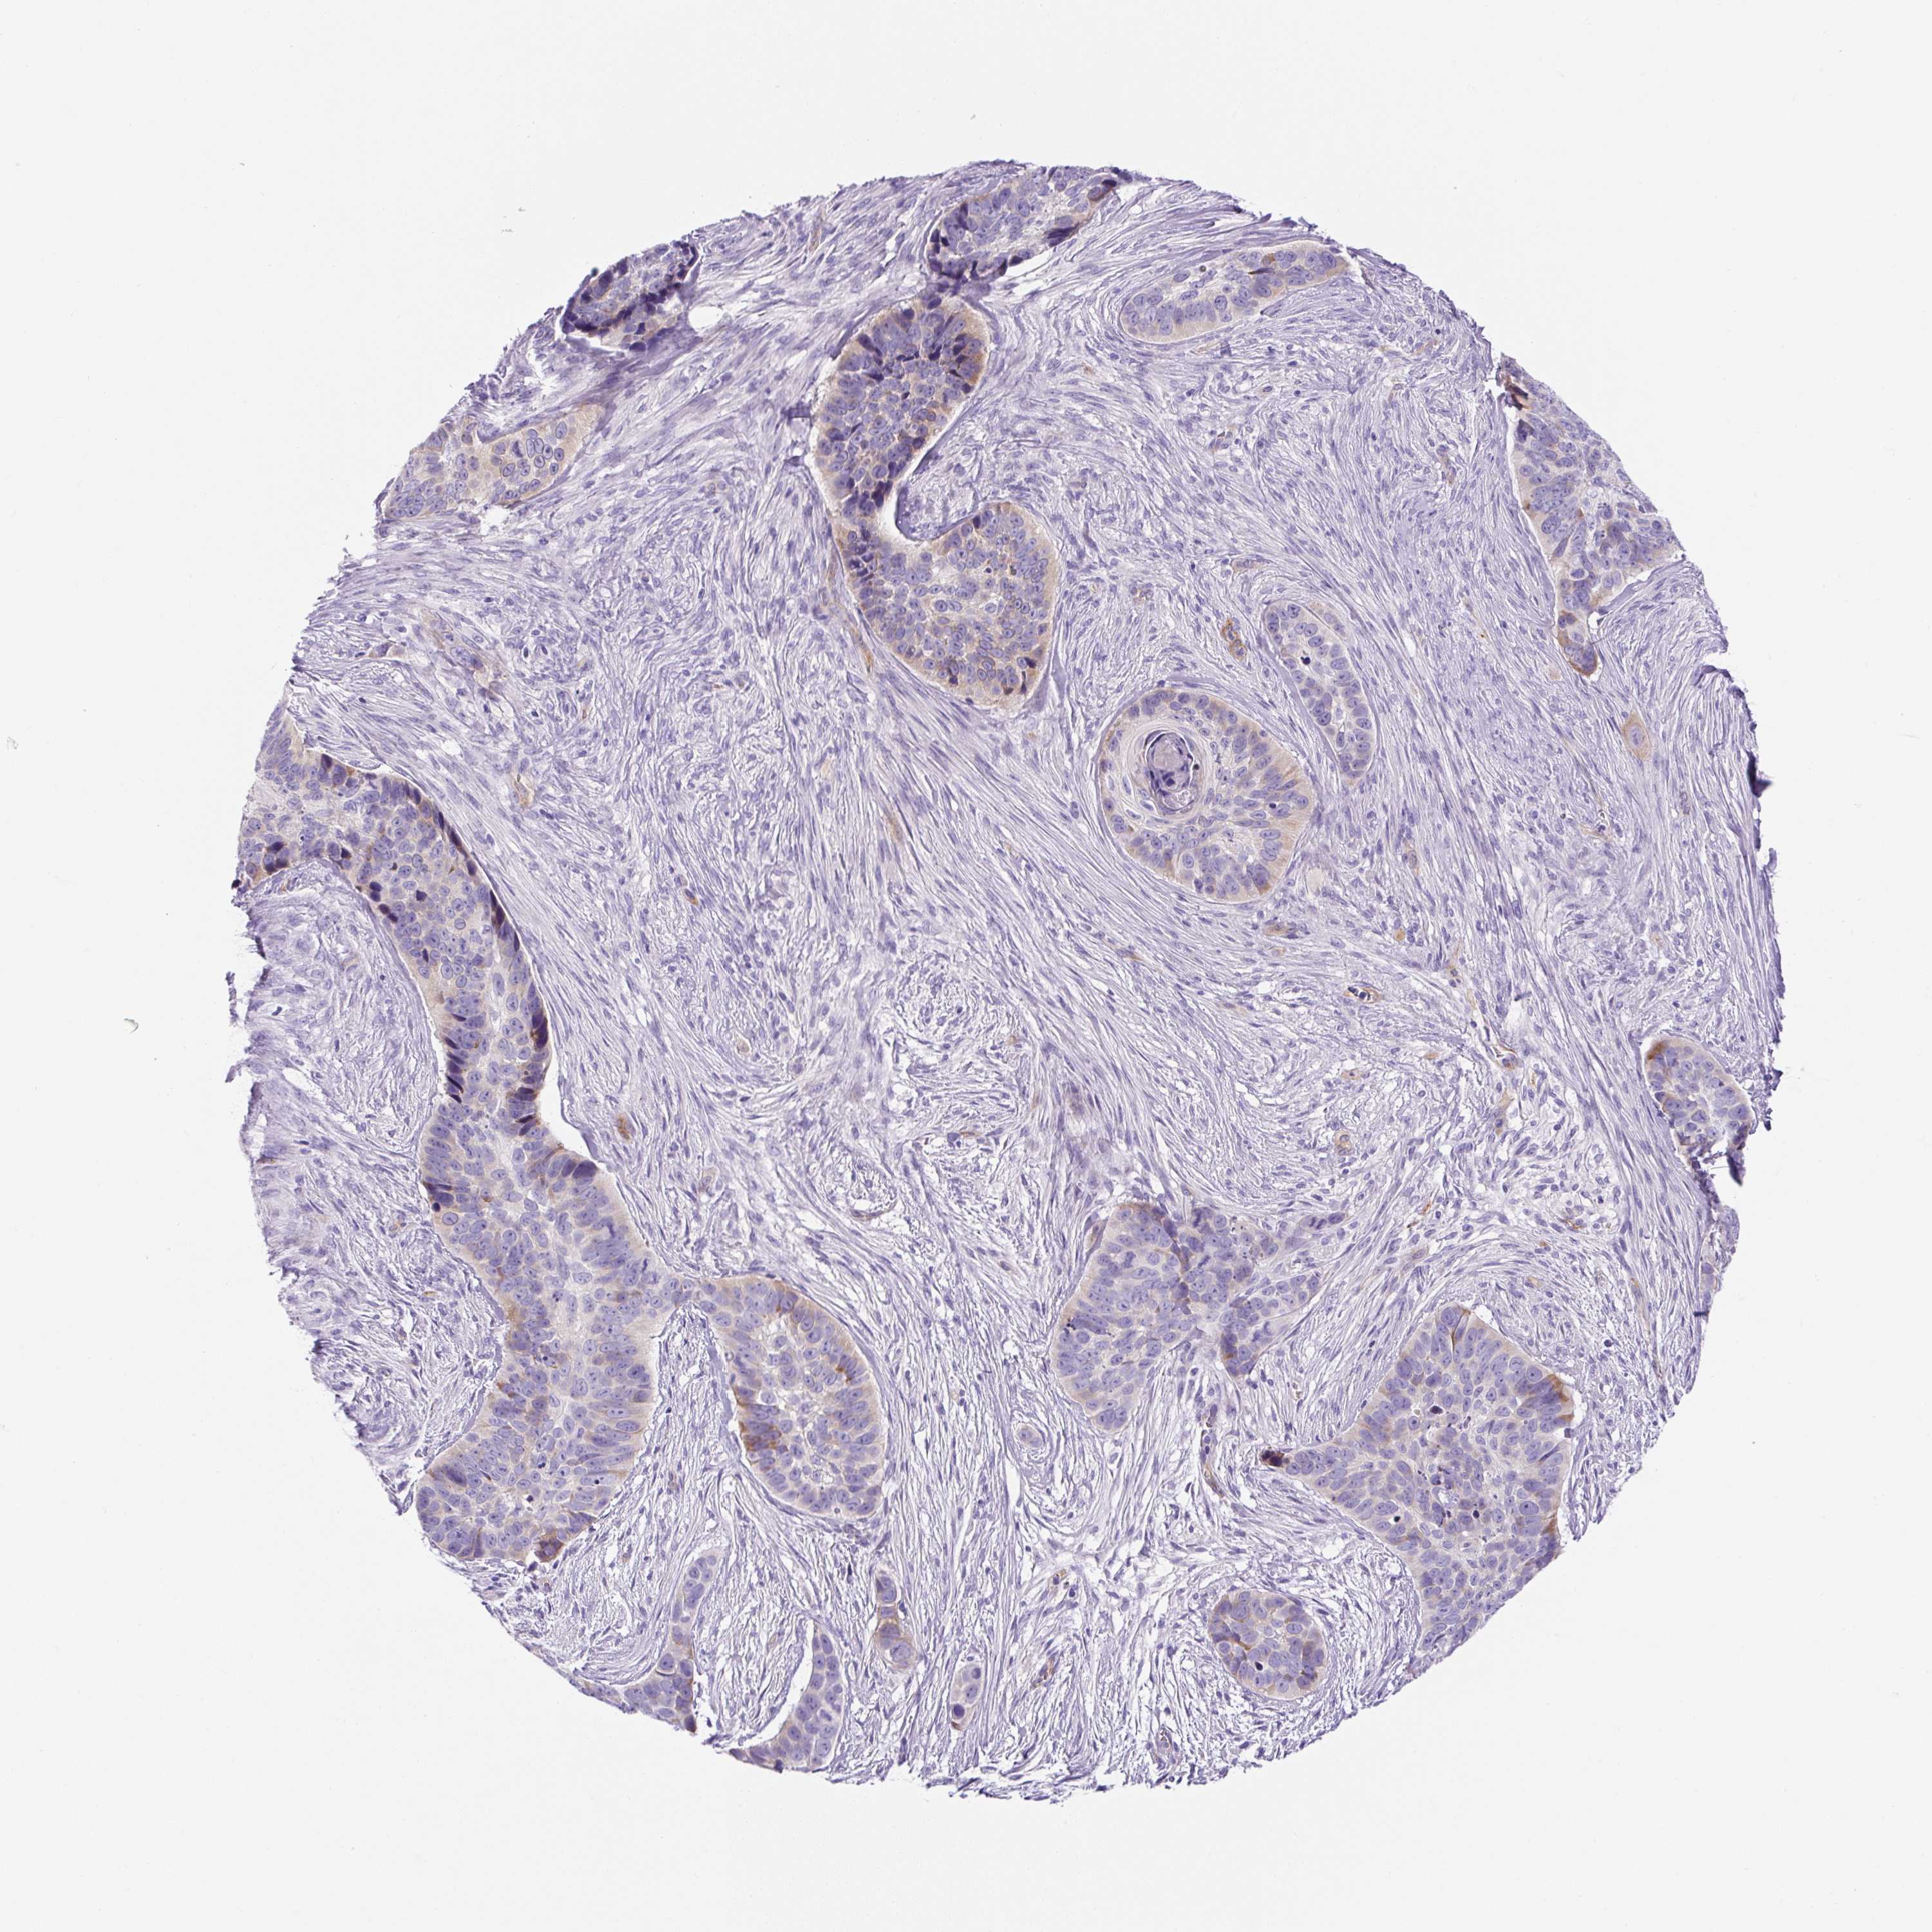

SKIN CANCER - Protein expressioni

A mouse-over function shows sample information and annotation data. Click on an image to view it in a full screen mode. Samples can be filtered based on level of antibody staining by selecting one or several of the following categories: high, medium, low and not detected. The assay and annotation is described here.

Antibody stainingi

Antibody staining in the annotated cell types in the current human tissue is reported as not detected, low, medium, or high, based on conventional immunohistochemistry profiling in selected tissues. This score is based on the combination of the staining intensity and fraction of stained cells.

Each image is clickable and will lead to virtual microscopy that enables deeper exploration of all samples and also displays staining intensity scores, fraction scores and subcellular localization as well as patient and tissue information for each sample.

Antibody HPA055240

Staining

High

Medium

Low

Not detected

Intensity

Strong

Moderate

Weak

Negative

Quantity

>75%

75%-25%

<25%

None

Location

Nuclear

Cytoplasmic/membranous

Cytoplasmic/membranous,nuclear

Basal cell carcinoma

Squamous cell carcinoma, NOS